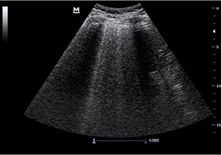

D1.  D2.

D2.

Figure D. In image D1, the TE7 Ultrasound machine is looking at the inferior vena cava (IVC). Image D2 shows the lung with ultrasound and D3 shows a cardiac assessment with smart measurements to check heart function. Images courtesy of Mindray Medical International.